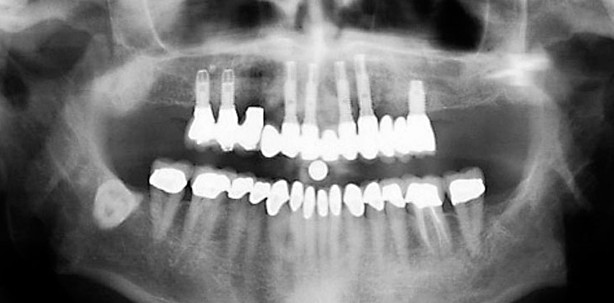

- die Zonenverteilung im Oberkiefer, wie sie sich in einem OPG darstellt.

Um festzustellen, ob axiale Implantate, geneigte Implantate oder das Zygoma-Implantatkonzept geeignet sein können, wird der Alveolarkamm in drei separate Zonen eingeteilt:

- Zone 1: von Eckzahn zu Eckzahn

- Zone 2: der Prämolarenbereich

- Zone 3: der Molarenbereich

Das Vorliegen oder der Mangel an ausreichendem Knochen in den verschiedenen Zonen hat einen großen Einfluss auf die Wahl der chirurgischen Technik (Tab. 1). Ist der Knochen in allen drei Zonen angemessen, können axiale Implantate eingesetzt werden (Abb. 8). Das geneigte Implantatkonzept sollte in Betracht gezogen werden, wenn die Zonen I und II ausreichend Knochen aufweisen (Abb. 9). Ist nur in Zone I ausreichend Knochen vorhanden, sollte das Zygomaehandlungskonzept in Betracht gezogen werden (Abb. 10). In den seltenen Fällen, in denen es in allen drei Zonen an ausreichendem Knochen fehlt, sollte das Konzept Quad-Zygoma in Erwägung gezogen werden (Abb. 11).